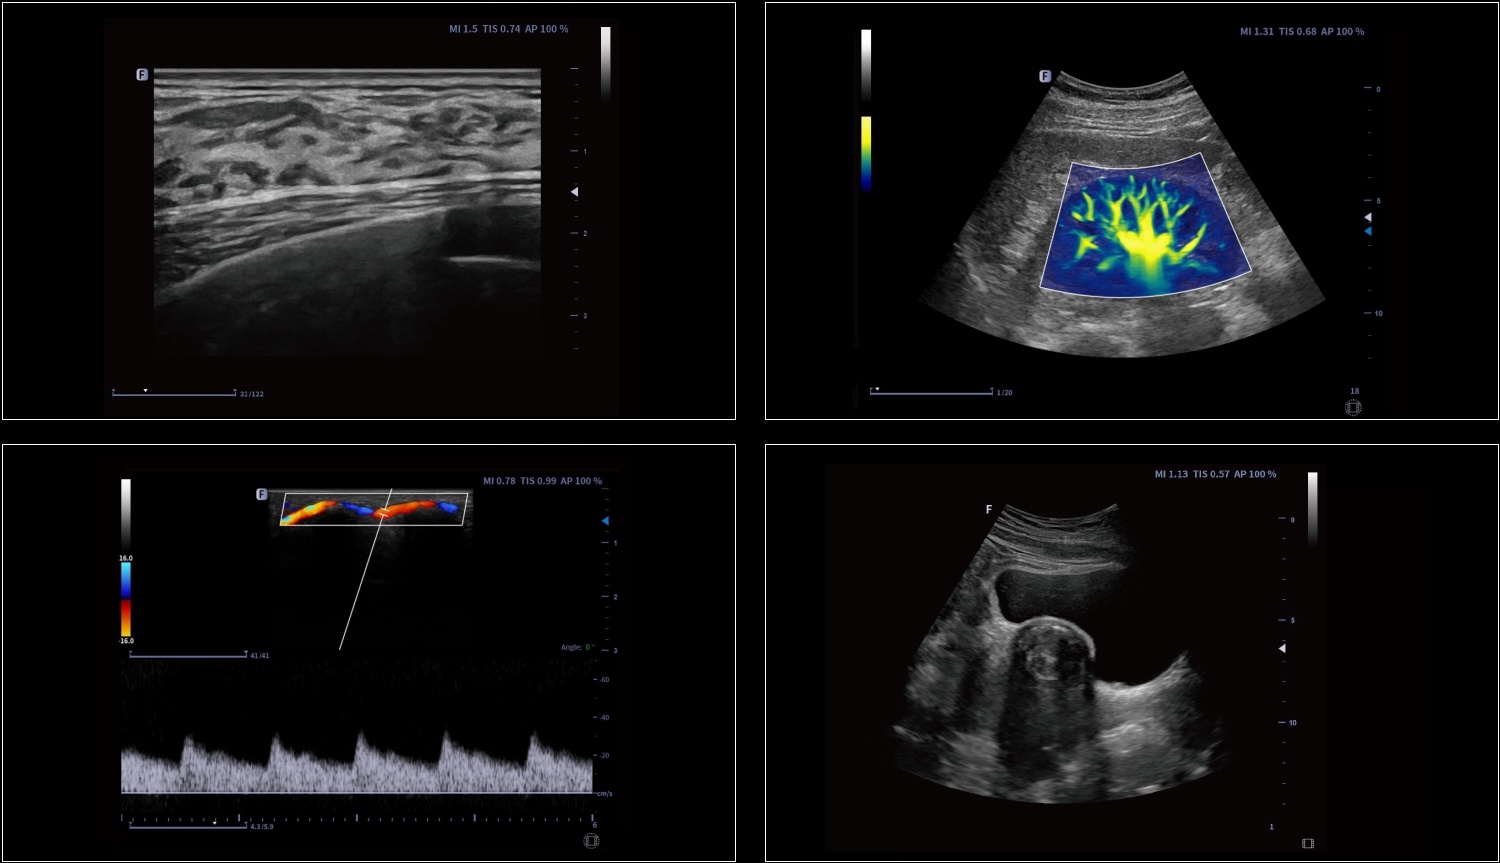

Technologia obrazowania ultrasonograficznego z inwersją impulsów i kontrastowaniem pozwala dokładnie wyodrębnić drugi harmoniczny kontrastowych mikropęcherzyków, co umożliwia uzyskanie obrazowania z wysokim stosunkiem kontrastu do tkanki oraz zapewnia bardziej szczegółową diagnozę kliniczną.

Elastografia w czasie rzeczywistym to nowa nieinwazyjna i bezbolesna technika, która pomaga określić twardość organów oraz innych struktur takich jak piersi czy tarczyca. Obrazowanie elastyczne dostarcza użytkownikom dynamicznych informacji wizualnych i pokazuje sztywność organów, co jest pomocne w bezpośredniej i ilościowej diagnozie oraz leczeniu.

Umożliwia ustawienie kursora M-trybu pod dowolnym kątem na cyfrowych obrazach dwuwymiarowych. Trzy linie próbkowania pozwalają lekarzowi mierzyć jednocześnie trzy pozycje, a każda linia próbkowania może być obrócona o 360°.

Stosowane do pomiaru wysokoprzepływowego przepływu krwi wewnątrz serca, wykazuje oczywiste zalety w ilościowej analizie zwężenia i niedomykalności.